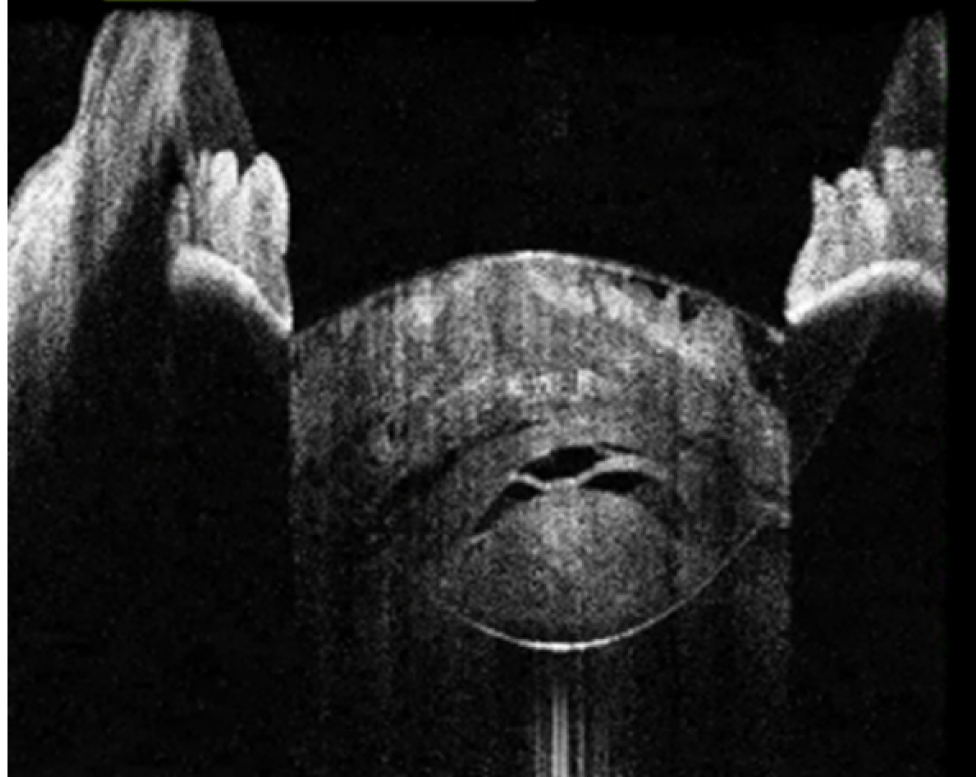

В исследование вошли 196 пациентов (250 глаз) с перезрелой катарактой. Пациенты были разделены на 2 группы (по 125 глаз в каждой группе). Всем пациентам интраоперационно с помощью интегрированной в операционный микроскоп И-ОКТ, Hi-R NEO (HAAG STREIT, Германия), определяли тип перезрелой катаракты (рис. 1–4).

Рис. 2. Тип 2 перезрелой катаракты: непрерывные гиперрефлективные полосы кортикальных волокон, множественные внутрихрусталиковые щели, оводнение хрусталика